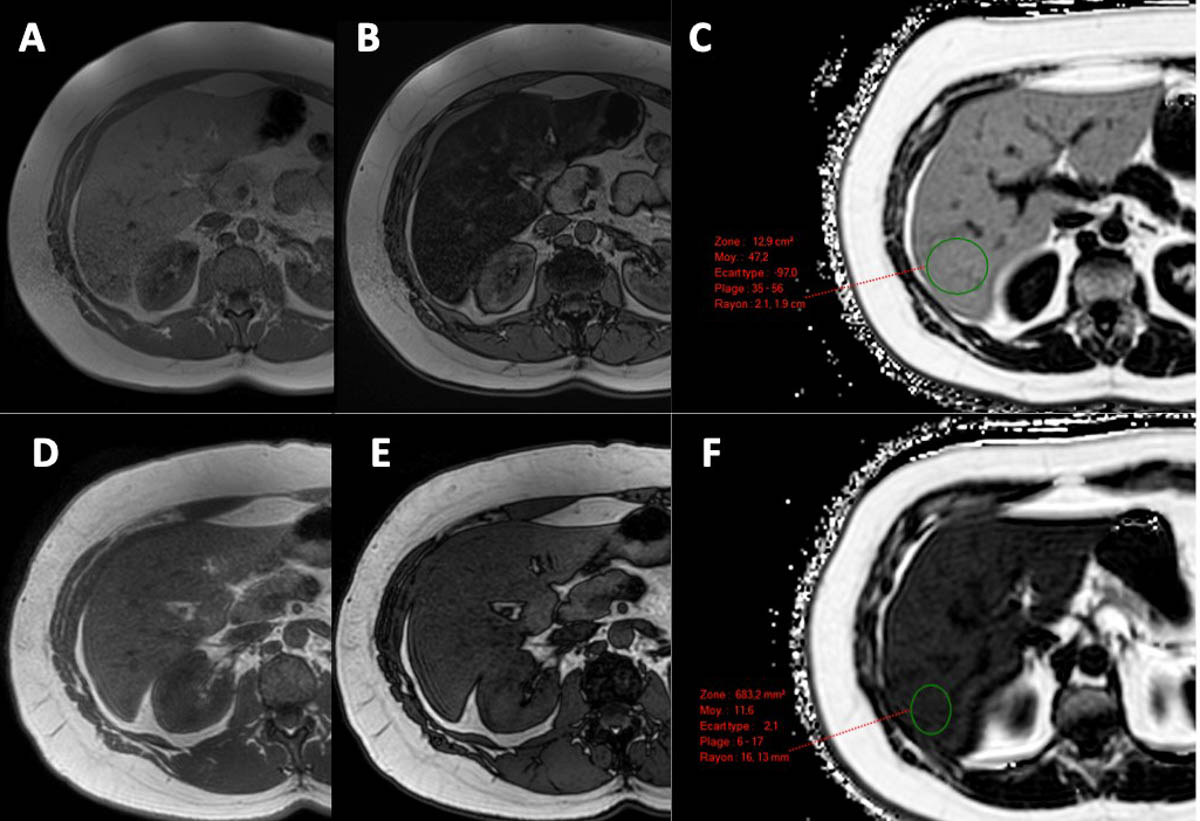

La stéatopathie hépatique, qu’elle soit liée ou non à l’alcool, est appelée à devenir la première cause de maladies chroniques du foie en Europe. Cette évolution incite à repenser les stratégies de dépistage. L’étude LiverScreen, la première vaste étude prospective européenne, a exploré ces enjeux en recrutant plus de 30 000 patients dans neuf pays, dont la France et l’Espagne. Grâce à l’élastométrie réalisée avec le Fibroscan, un examen non invasif recommandé par l’Organisation mondiale de la santé, elle a permis de détecter une fibrose significative chez 5 % des participants, soulignant l’importance d’un dépistage ciblé. Ces résultats mettent en lumière le rôle majeur des facteurs de risque tels que l’obésité, le diabète de type 2 et la consommation excessive d’alcool, éléments essentiels dans l’évaluation clinique.

Face à la prévalence élevée de facteurs de risque dans la population européenne, dépister systématiquement tous les individus serait inefficace et coûteux. Le consensus scientifique penche en faveur d’un dépistage opportuniste, ciblé sur les patients présentant au moins un facteur de risque, à partir de l’âge de 40 ans. Le score LiverRisk, élaboré par le consortium LiverScreen, exploite six critères simples pour orienter les patients vers un diagnostic approfondi, notamment par Fibroscan. Cette méthode s’avère particulièrement précieuse pour détecter précocement la fibrose hépatique, facteur clé dans l’évolution vers la cirrhose ou le cancer du foie.